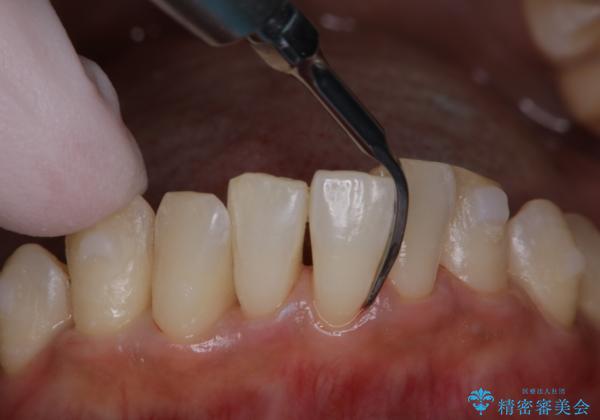

アタッチメントが歯に付くと、表面が凸凹し磨き残しが多くなったりと、プラークや歯石・着色がつきやすくなることがあります。

矯正治療中もPMTCを定期的に行い、専門的な機械でしっかりと汚れを除去することがおススメです。